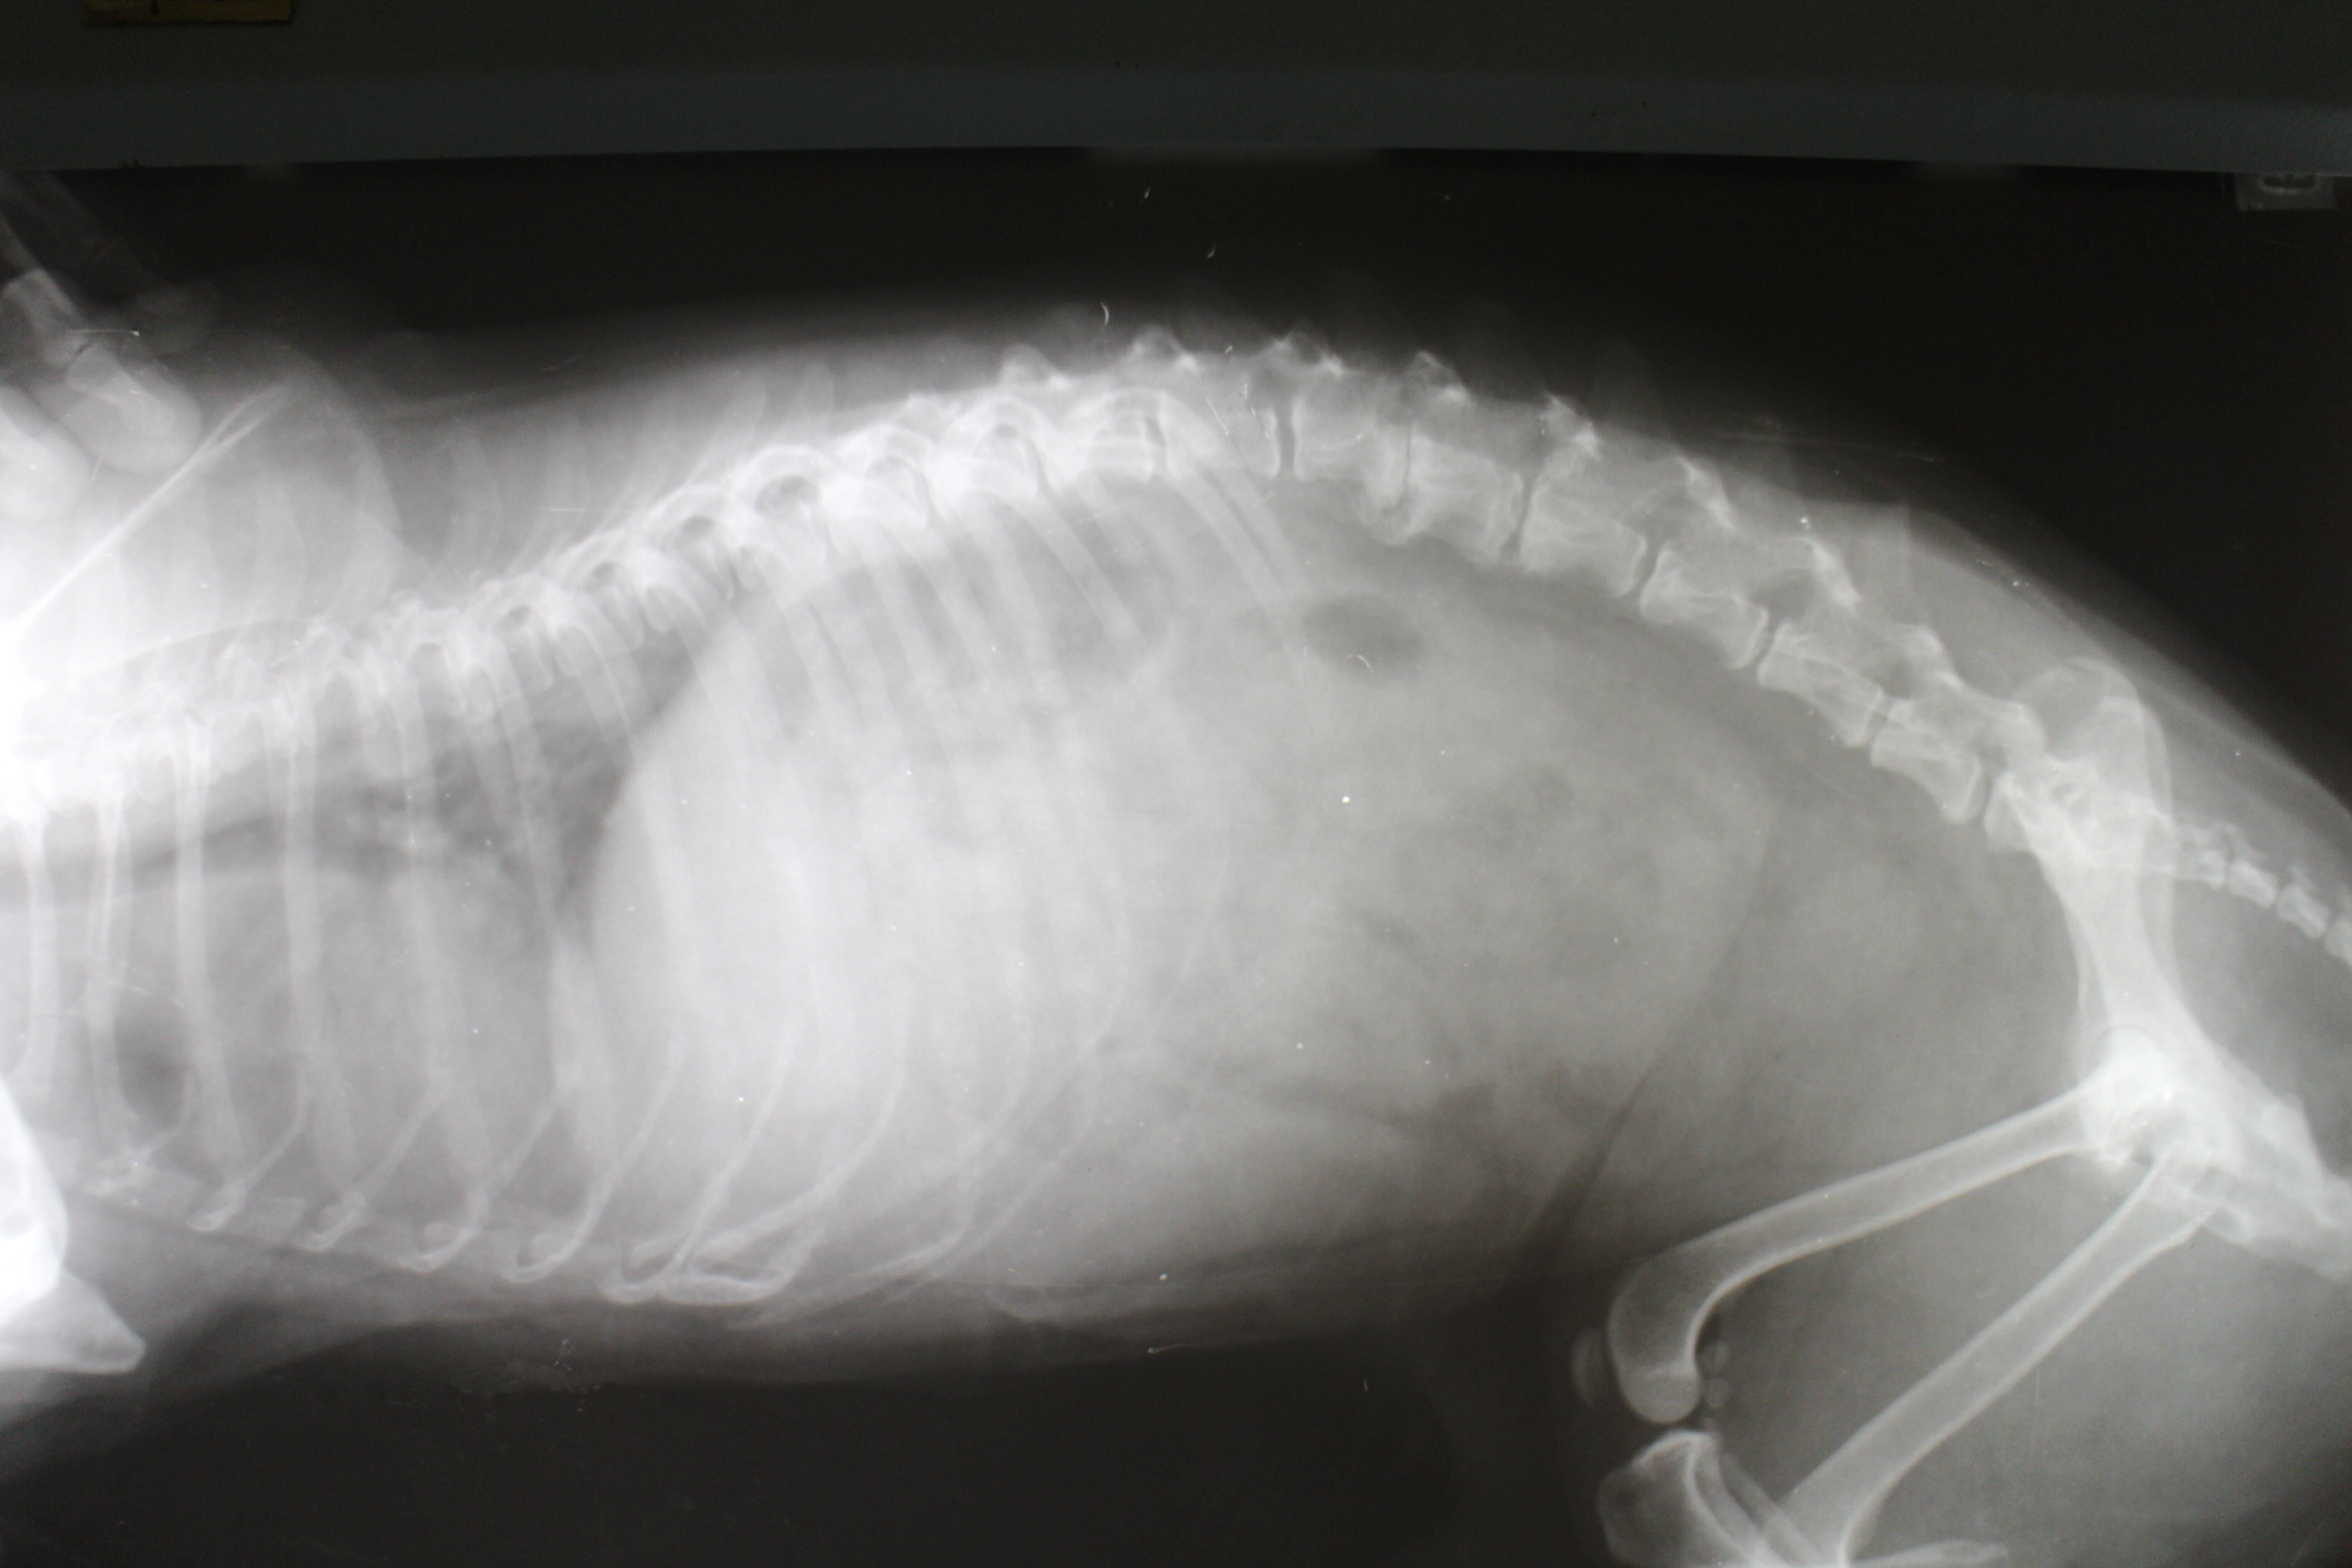

Successful Treatment for Canine Spinal Injuries

Lab tests have shown that an injection of a liquid polymer known as polyethylene glycol (PEG), if administered within 72 hours of serious spinal injury, can prevent most dogs from suffering permanent spinal damage. Even when the spine is initially damaged to the point...